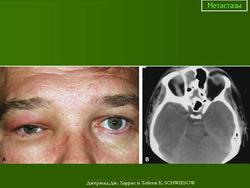

Метастазы. Пт, 29/07/2011 - 11:59 #1 Катенёв Валенти... Не на сайте Был на сайте: 7 лет 2 месяцев назад Зарегистрирован: 22.03.2008 - 22:15 Публикации: 54876 Нейроэктодермальная опухоль.Приложения:

Нейроэктодермальная опухоль.